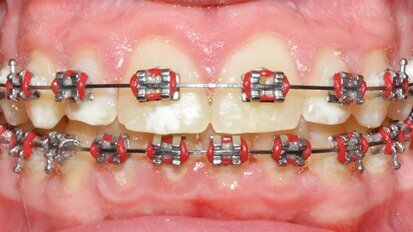

Protocollo sperimentale per la gestione dei tessuti duri durante il trattamento ortodontico

L’ortodonzia è la branca dell’odontoiatria che si occupa di prevenzione, diagnosi e trattamento delle alterazioni scheletriche a livello del massiccio ...